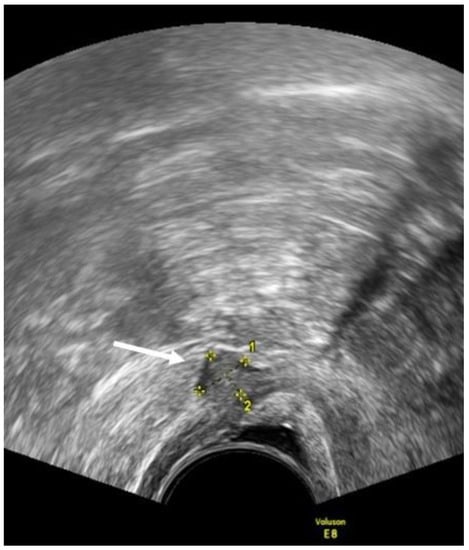

- Leonardi, M.; Martins, W.P.; Espada, M.; Arianayagam, M.; Condous, G. Proposed technique to visualize and classify uterosacral ligament deep endometriosis with and without infiltration into parametrium or torus uterinus. Ultrasound Obstet. Gynecol. 2019, 55, 137–139. [Google Scholar] [CrossRef]